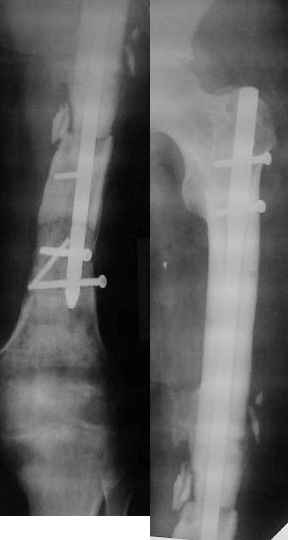

Re: Ложный сустав в/3 плечевой кости!

Неудачный остеосинтез пластиной: поломка винтов, миграция фиксатора. После удаления пластины сформировался гипопластический ложный сустав нижней трети бедренной кости, укорочение н/к 5 см. Выполнялся дистакционный остеосинтез аппратом Илизарова на штифте. Зона ложного сустава "не открывалась". Через 10 месяцев, когда даже регенерат полностью перестроился, консолидации в зоне ложного сустава не наступило, несмотря на стабильную фиксацию и постоянную компрессию(штифт+аппрата на 4 кольцах).